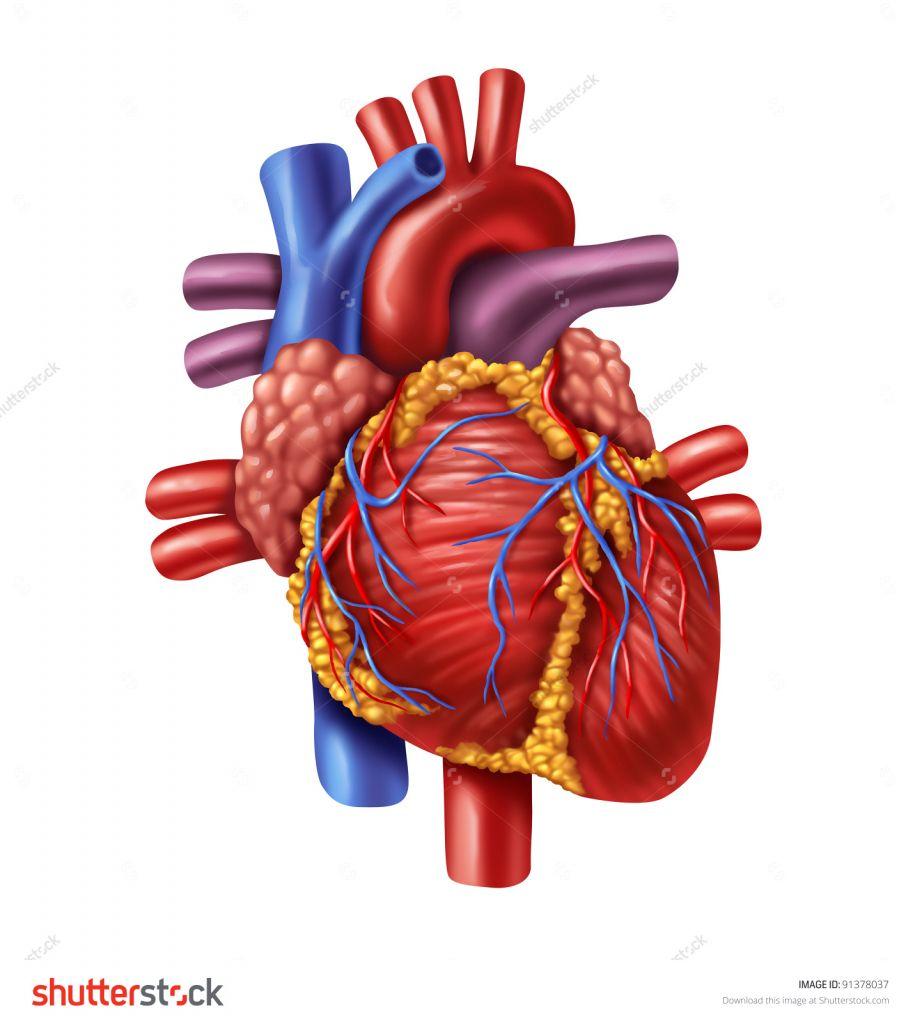

Human Heart Drawing Outline at GetDrawings | Free download  3d anatomy human heart

3d anatomy human heart  Show me a diagram of the human heart? Here are a bunch! - Interactive Biology, with Leslie Samuel

Human Heart Sketchbook study by bluesytealyren on DeviantArt | Human heart drawing, Anatomical  3d human heart

3d human heart  Animated Realistic Human Heart - Medically 3D asset

Heart Anatomy Human Heart Images Hd 3D - Dreaming Arcadia  Anatomical Heart Drawing at GetDrawings | Free download

Realistic detailed 3d human anatomy heart Vector Image  3D human heart model - TurboSquid 1149348

Heart Anatomy Human Heart Images Hd 3D - Dreaming Arcadia  Realistic Human Heart 3D model | CGTrader

Heart Anatomy Human Heart Images Hd 3D - Dreaming Arcadia  Pin on Body Parts Drawings

Heart Diagram Human Heart Images Hd 3D - img-Badr  Real Human Heart Drawing at GetDrawings | Free download